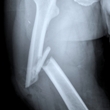

A fracture or broken bone occurs when a force exerted against a bone is stronger than it can structurally withstand. A bone fracture is a medical condition in which a bone is cracked or broken. While many fractures are the result of high force impact... read more